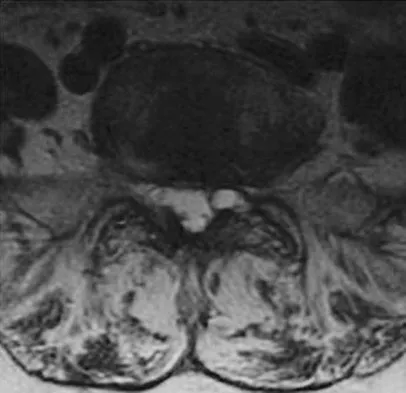

A 73-year-old woman reports a 4-month history of severe left-sided posterior buttock pain and left leg pain. The leg pain radiates into the left lateral thigh and posterior calf with cramping. Examination reveals mild difficulty with a single-leg toe raise on the left side and a diminished ankle reflex. There is also a significant straight leg raise test at 45 degrees which exacerbates symptoms. An MRI scan is shown in Figure 4. What is the most appropriate treatment at this time?

Explanation

Lumbar spinal stenosis with lumbar radiculopathy can be commonly caused by a synovial cyst arising from the facet joints. Lyons and associates reported on the surgical treatment of synovial cysts in 194 patients. Of the 147 with follow-up data, 91% reported good pain relief and 82% had improvement of their motor deficits. Epstein reported a 58% to 63% incidence of good/excellent results and a 38 to 42 point improvement on the SF-36 Physical Function Scale. It was also suggested that since the presence of a synovial cyst indicates facet pathology, possible fusion should be considered in these patients, especially those with underlying spondylolisthesis. Lyons MK, Atkinson JL, Wharen RE, et al: Surgical evaluation and management of lumbar synovial cysts: The Mayo Clinic Experience. J Neurosurg 2000;93:53-57. Khan AM, Synnot K, Cammisa FP, et al: Lumbar synovial cysts of the spine: An evaluation of surgical outcome. J Spinal Disord Tech 2005;18:127-131.

References:

- Epstein NE: Lumbar laminectomy for the resection of synovial cysts and coexisting lumbar spinal stenosis or degenerative spondylolisthesis: An outcome study. Spine 2004;29:1049-1055.